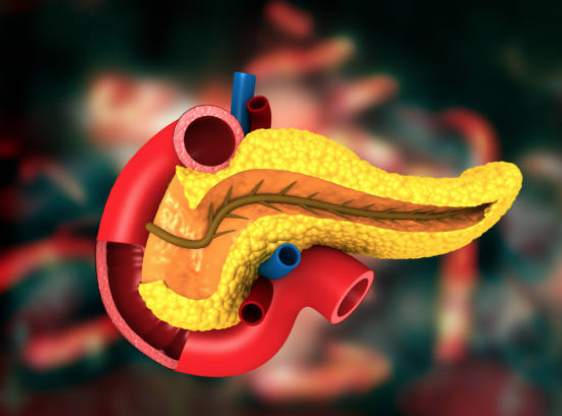

Жовч у процесі травлення допомагає розщеплювати жири та засвоювати жиророзчинні вітаміни типу (A, D,...